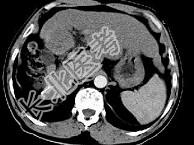

- 单项选择题女性患者,56岁, 腹胀、双下肢浮肿、乏力、食欲不振,影像所见如下图, 最佳的诊断是 ( )

A、肝炎后肝硬化并肝癌

B、局限性脂肪肝

C、原发性肝癌

D、血吸虫肝硬化并肝癌

E、酒精性肝硬化并肝血管瘤